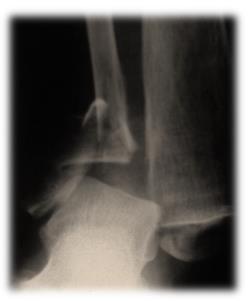

Пациент С. 64 лет, страдающий диабетом II типа, тяжелое течение. Закрытый перелом наружной внутренней лодыжек. Малоинвазивный остеосинтез лодыжек.

Рисунок 3Рисунок 4Рисунок 5(а)Рисунок 5(б)Рисунок 6 (а,б) Результат через 6 недель после операции.